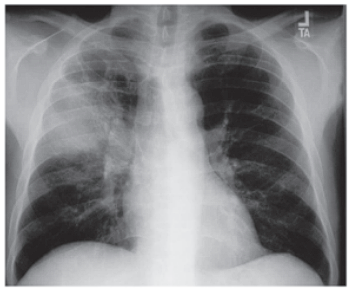

Uma mulher de 22 anos de idade, mora com seu único filho de 3 anos de idade, refere ter múltiplos parceiros e faz prevenção ocasional de DST com preservativos masculinos. A paciente procurou uma Unidade Básica de Saúde (UBS) com queixa de dispneia e tosse que ocorre há 3 meses, inicialmente seca, tendo evoluído com expectoração mucopurulenta e presença de sangue. Ela relata perda de apetite, febre de até 38,5 °C, principalmente no período da tarde, e sudorese noturna. Informa ainda que recebeu o diagnóstico de HIV há 2 anos. Faz uso de medicação antirretroviral de forma irregular há 6 meses. O exame físico pulmonar da paciente mostrou: murmúrio vesicular presente, distribuído difusamente com roncos ocasionais que melhoram com a tosse. Contagem de células CD4: 242 células/mm³ (valor de referência: superior a 900 células/mm³) e radiografia do tórax, como mostra a imagem a seguir.